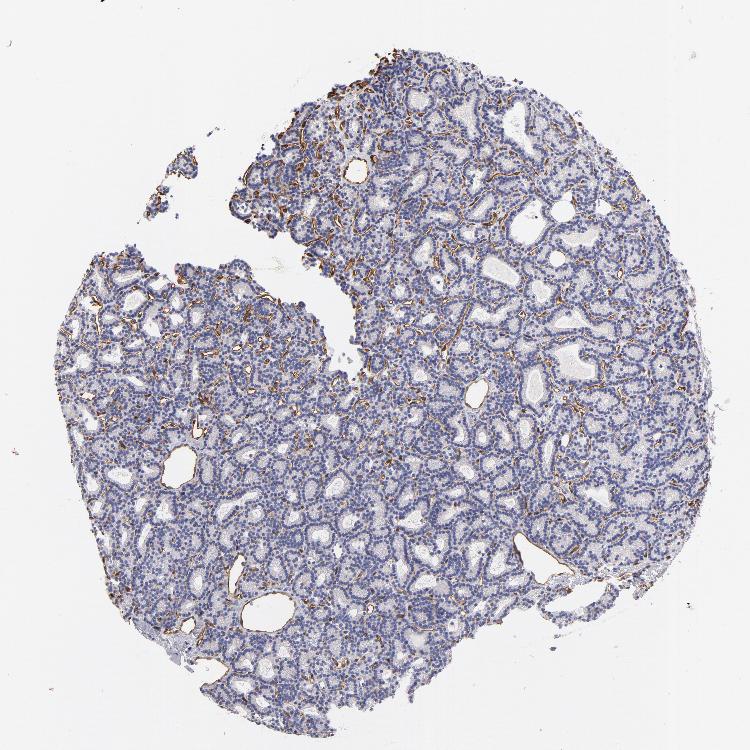

TISSUE PRIMARY DATA PARATHYROID GLAND Show tissue menu

Parathyroid gland

PARATHYROID GLAND - Antibody stainingi

Antibody staining in the annotated cell types in the current human tissue is reported as not detected, low, medium, or high, based on conventional immunohistochemistry profiling in selected tissues. This score is based on the combination of the staining intensity and fraction of stained cells.

Each image is clickable and will lead to virtual microscopy that enables deeper exploration of all samples and also displays staining intensity scores, fraction scores and subcellular localization as well as patient and tissue information for each sample.

Antibody HPA002279

Glandular cells Not detected